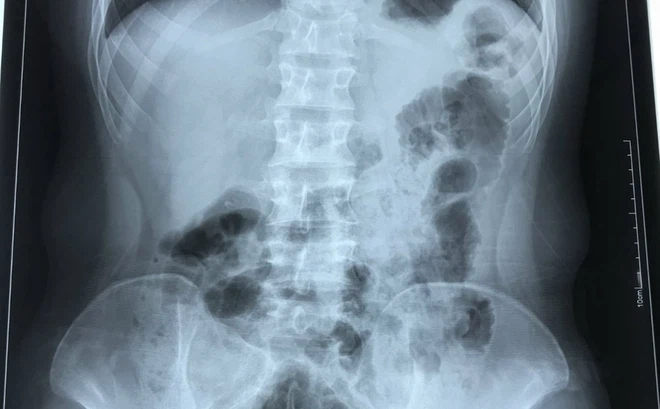

Phim chụp X-quang của bệnh nhân cho thấy tình trạng phủ tạng đảo ngược với trái tim nằm bên lồng ngực phải (Ảnh: BVCC)

Đặc biệt, bác sĩ phát hiện trái tim của nam thanh niên nằm bên lồng ngực phải, ở vị trí đảo ngược so với người bình thường. Gia đình cho biết, trái tim và các tạng trong cơ thể H. đều nằm ở vị trí đối lập so với mọi người.

Theo bác sĩ, đảo ngược phủ tạng là tình trạng bẩm sinh, trong đó các cơ quan nội tạng trong ngực, bụng bị đảo ngược, phản chiếu theo mặt phẳng đứng dọc so với vị trí bình thường. Các phủ tạng có thể bị đảo ngược hoàn toàn hoặc chỉ một vài cơ quan đơn thuần.

Đây là một dạng dị tật có tính di truyền gen lặn tương đối hiếm gặp, với tỷ lệ 1/10.000 dân, trong đó có khoảng 5-10% có dị tật tim bẩm sinh, còn lại có cuộc sống bình thường, không ảnh hưởng đến sức khỏe.